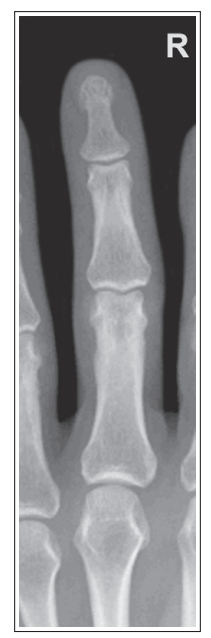

Unequal concavity between phalanges and MCs

Hand was slightly externally rotated

Distal phalanges are foreshortened and distorted

Hands and fingers were flexed